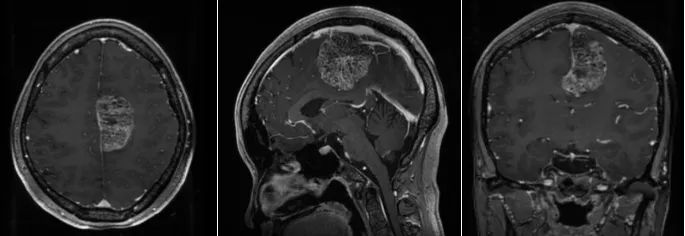

随后,张女士一家前往上海市静安区中心医院(华山医院静安分院)就医。头部MRI检查显示,脑肿瘤位于左脑额顶叶功能区,血液供应极其丰富,切除困难,手术风险极大。

在这种棘手的情况下,华山医院鲍伟民教授和顾昕主任进行了严格的术前讨论和评估。顾昕认为,该病人左额顶功能区极大的脑膜瘤,手术指征非常明确。考虑到脑膜瘤体积大,血液供应丰富,术中容易出现大出血。同时,切除肿瘤时,容易损伤周围重要的动静脉,引起不可逆的大面积脑梗死和回流障碍,术后出现肢体偏瘫麻木、脑肿胀、脑出血甚至昏迷死亡。讨论结束后,建议在导航下精确定位,保护中央沟静脉和中央前后,分层切除肿瘤。